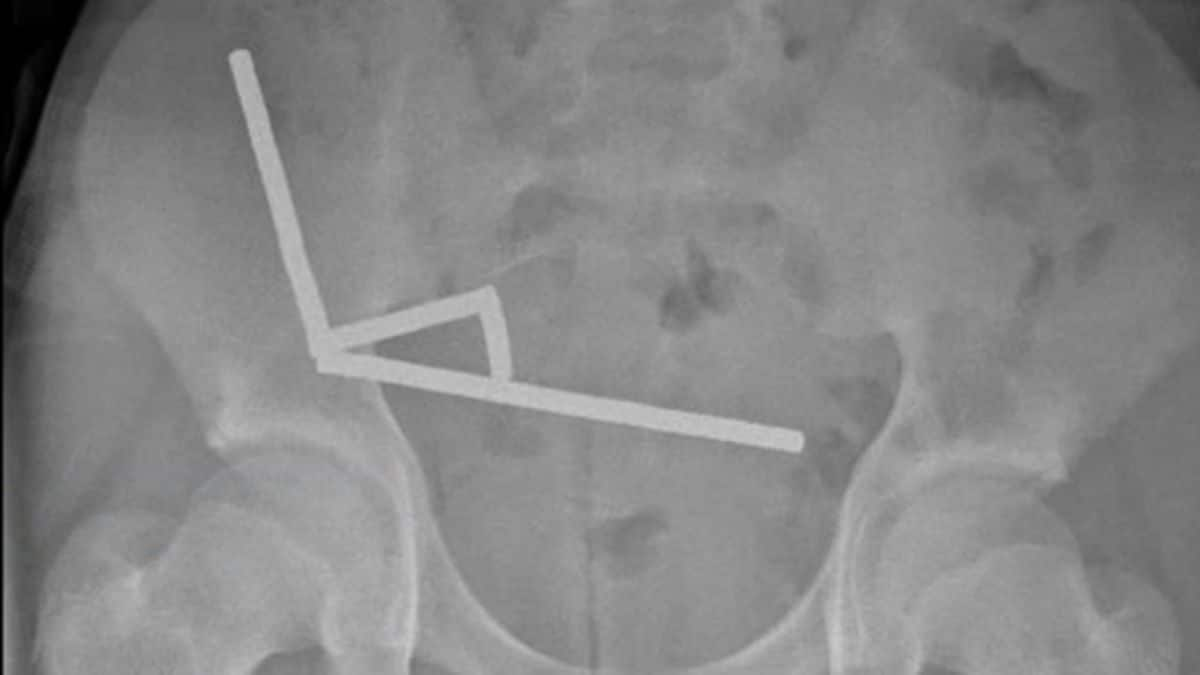

I dischi magnetici si erano collegati con forza gli uni agli altri all'interno dell'intestino del ragazzo formando lunghe file, come mostrano le radiografie. Gli esiti sui tessuti interni sono stati catastrofici, determinando necrosi da pressione e la necessità di intervenire urgentemente per rimuovere parte dell'apparato digerente. Danni e conseguenti infezioni sui tessuti intestinali avrebbero avuto in breve tempo un esito mortale. Fortunatamente l'invasivo e delicato intervento chirurgico è stato un successo e il ragazzo è stato dimesso in buone condizioni dopo otto giorni di ricovero.